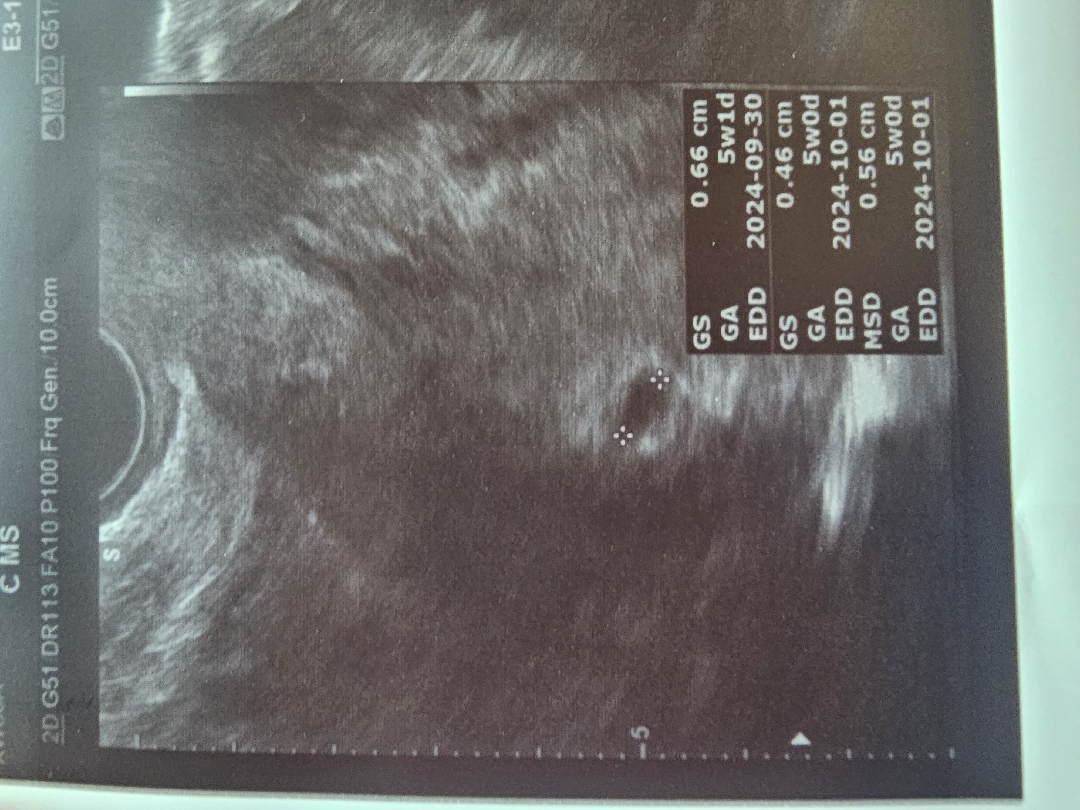

오늘 드디어 춈파보고왔어요!! 두근.. 5주 0일 이네요^^